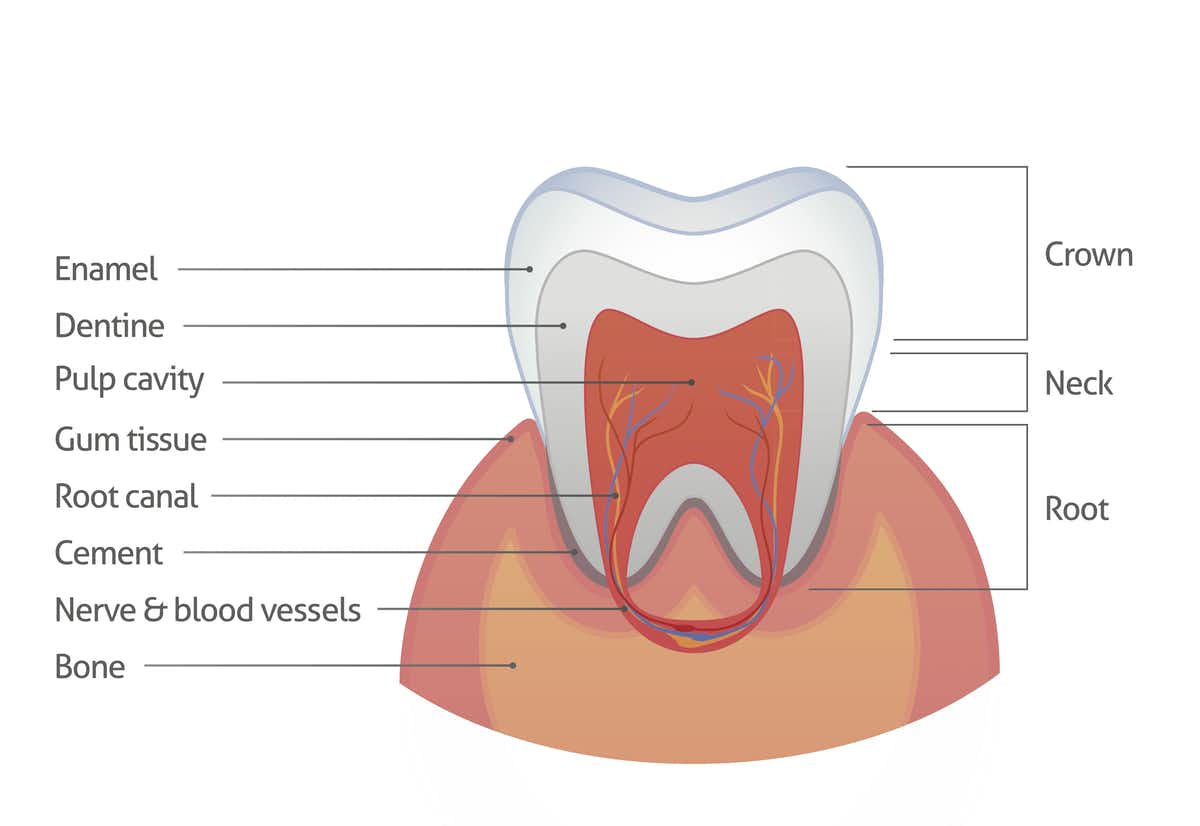

Tooth Enamel Structure

Tooth Enamel Structure